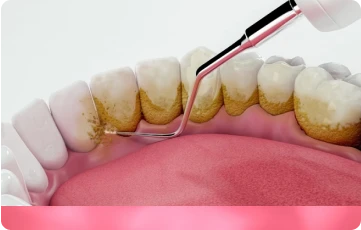

Dịch vụ cạo vôi răng giá rẻ tại Long Thành, Đồng Nai được thực hiện bởi đội ngũ bác sĩ giàu kinh nghiệm, tận tâm và được hỗ trợ bởi các thiết bị công nghệ tiên tiến. Chúng tôi sử dụng máy siêu âm hiện đại để loại bỏ mảng bám và vôi răng một cách nhanh chóng, chính xác, đồng thời đảm bảo không gây đau nhức hay ảnh hưởng đến men răng và nướu.

Quá trình làm sạch vôi răng tại Thủ Đức không chỉ tập trung vào việc loại bỏ mảng bám mà còn giúp ngăn ngừa các bệnh lý răng miệng như viêm nướu, hôi miệng hay viêm nha chu. Công nghệ siêu âm được ứng dụng để đảm bảo việc làm sạch diễn ra nhanh chóng, không đau và không gây tổn hại đến men răng hay nướu.